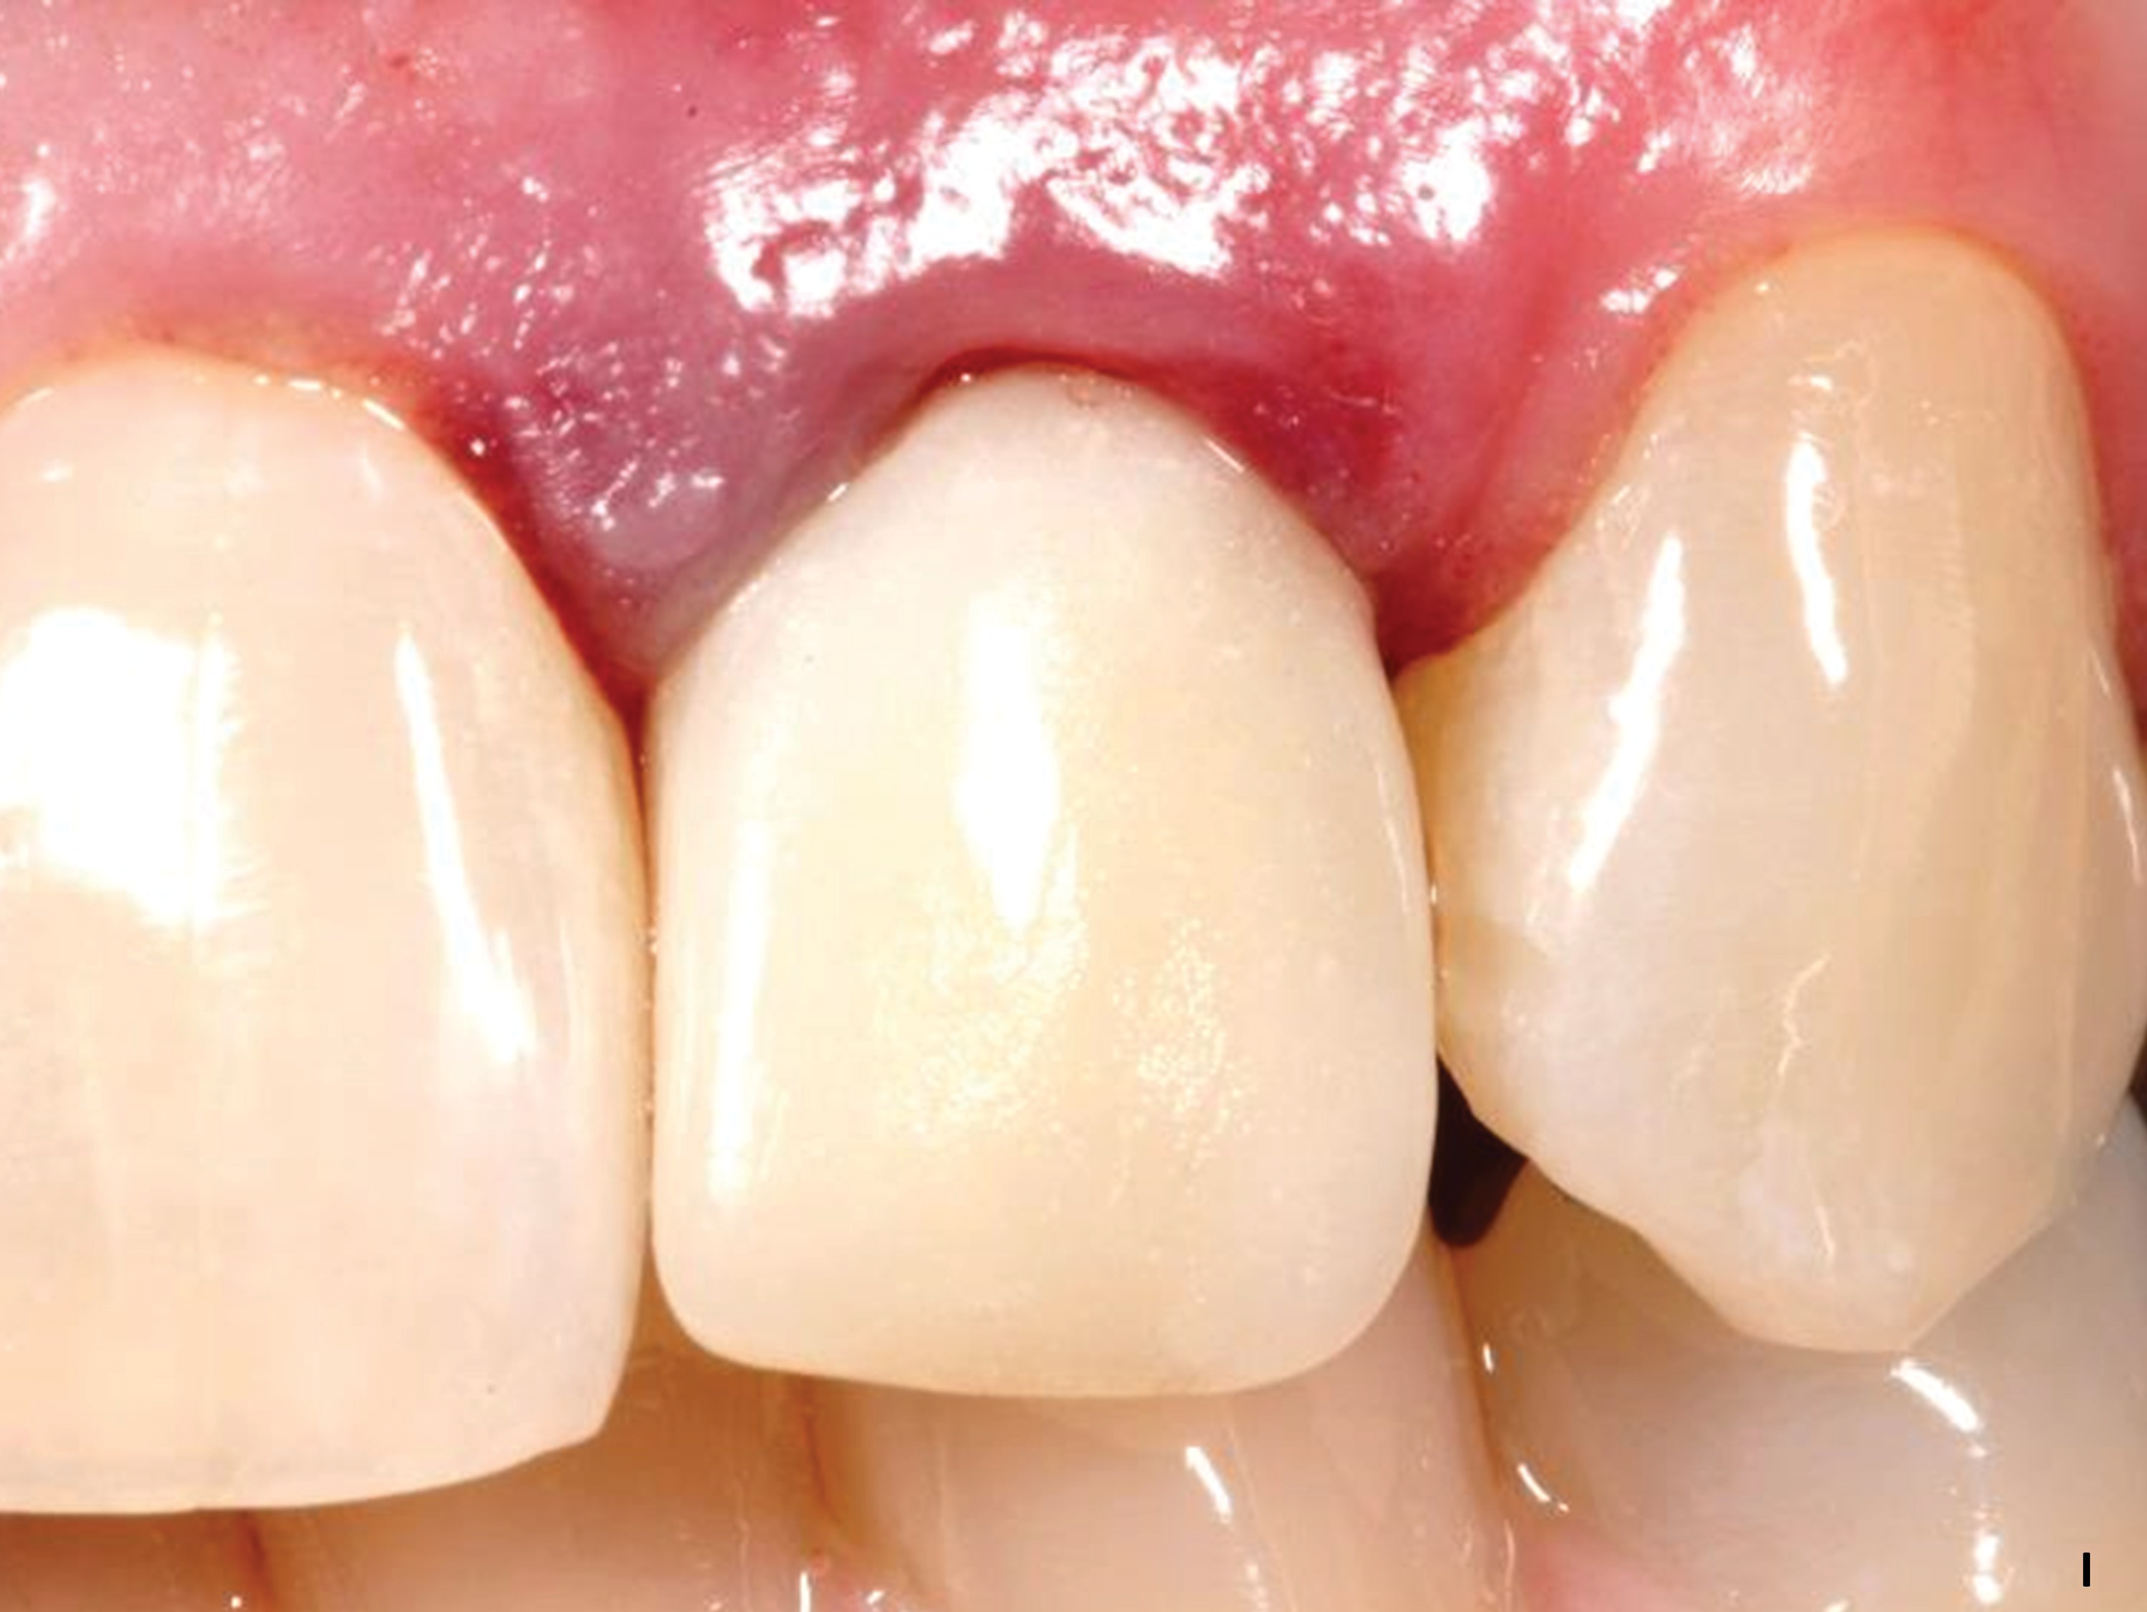

Fig 7. A case (Fig 7 through Fig 16) is presented demonstrating construction of a fixed provisional temporary crown at site No. 10, beginning with an implant placed at the site.

Figure 7

Fig 14. The provisional crown is inserted on the day of surgery. Note the height of the gingiva.

Figure 14